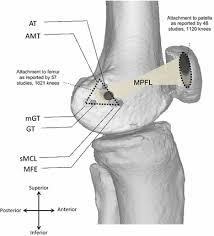

Medial Gastrocnemius Origin And Insertion / Why You Must Include The Seated Calf Raise Exercise - The medial and the lateral head.. A systematic review of anatomy. Femoral insertion between the medial femoral epicondyle, the adductor tubercle and the gastrocnemius tubercle, just superior to origin and insertion of the medial patellofemoral ligament: Lateral head from lateral surface of femoral lateral condyle insertion: Understanding the true anatomical origin and insertion of the mpfl is critical to successful reconstruction. The two medial trigger points lie in the medial head of the gastrocnemius, with the upper trigger point found just below the crease of the knee, and the lower.

Key facts about the gastrocnemius muscle. The two principle muscles are the iliacus and the psoas, collectively, they are called the iliopsoas. Running from a triangular space between the adductor tubercle, medial femoral epicondyle and gastrocnemius tubercle and inserts onto the superomedial aspect of the patella. Understanding the true anatomical origin and insertion of the mpfl is critical to successful reconstruction. It runs from its two heads just above the knee to the heel, a three joint muscle (knee, ankle and subtalar joints). Both heads of gastrocnemius join with the tendon of soleus and insert into the calcaneal tuberosity. The fibers of each head mirror each other as they travel obliquely toward the central tendon separating them, creating a. By brent brookbush ms, pes, ces, cscs, acsm h/fs. Gluteus maximus extends thigh at hip as in stair climbing, backswing of leg as when iliopsoas most muscles that act on the femur originate on the hip bone. The gastrocnemius originates with two heads: Lower posterior surface of the femur above the medial condyle. Understanding the true anatomical origin and insertion of the mpfl is critical to successful reconstruction. A medial gastrocnemius strain is an injury to the calf muscle that is also known as tennis leg.

Pelvic muscles primary action, insertion, and origin. Running from a triangular space between the adductor tubercle, medial femoral epicondyle and gastrocnemius tubercle and inserts onto the superomedial aspect of the patella. Plantarflexion of the foot at the ankle, assists with flexion. Key facts about the gastrocnemius muscle. Explained beautifully in an illustrated and interactive way.

The gastrocnemius muscles are very powerful. Medial head from posterior nonarticular surface of medial femoral condyle; Insertion the muscle inserts medially, in association with the achilles tendon on the calcaneus, or independently on calcaneus. Plantarflexion of the foot at the ankle, assists with flexion. Understanding the true anatomical origin and insertion of the mpfl is critical to successful reconstruction. Thoracic and lumbar vertebrae, ribs and iliac crest insertion: Femoral insertion between the medial femoral epicondyle, the adductor tubercle and the gastrocnemius tubercle, just superior to origin and insertion of the medial patellofemoral ligament: (bottom) the lateral collateral ligament can now be seen arising from lateral femoral condyle, coursing towards its it overlies the lateral gastrocnemius muscle distal to the muscle's origin, and runs along its lateral aspect. Lower posterior surface of the femur above the medial condyle. Muscle anatomy of the gastrocnemius includes origin, insertion, action, innervation and origin: Learn the gastrocnemius recession surgical technique with step by step instructions on orthoracle. Posterior part of the medial condyle and the adjoining part of the femur. It is possible that anatomical differences of tendinous structures at the mg origin and insertion sites may influence how much of the changes in mtu length are.